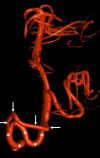

Figure 5. Arteriogram noting a fenestrated left vertebral artery (arrow) at the vertebrobasilar junction

The left vertebral artery is noted with asterisks. Also, note the basilar artery (BA) and right vertebral artery (RVA)